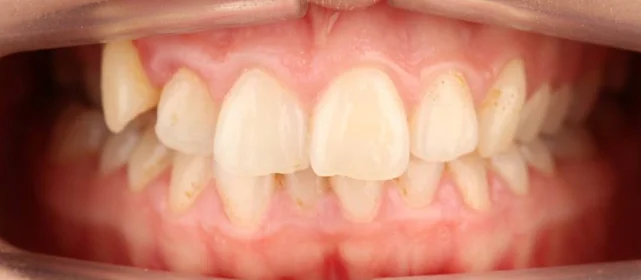

Нарушение соотношения челюстей и неправильное положение зубов — зубные ряды смыкались некорректно, зубы стояли со смещением.

Проблема: Пациентку не устраивало положение зубов и то, как смыкаются челюсти. Зубы стояли неровно, ряды сходились неправильно.